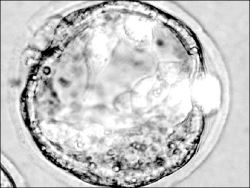

Madrid, 31 de octubre. Críticas de la Iglesia católica y aplausos de la comunidad científica acogieron el decreto del gobierno español que regula la investigación con células madres embrionarias, que posibilitará la cura de enfermedades como el Alzheimer, el Parkinson y la diabetes.

La vicepresidenta primera del gobierno, María Teresa Fernández de la Vega, y la ministra de Sanidad, Elena Salgado, presentaron el decreto aprobado el viernes en consejo de ministros ordinario, como un "paso importante" en la batalla contra enfermedades hoy por hoy incurables.

Siguiendo el ejemplo de países como Gran Bretaña o Suecia, España contará con dos centros pioneros. El Centro de Medicina Regenerativa de Barcelona existirá jurídicamente este mismo mes de noviembre para poder poner en marcha luego un Banco de Líneas Celulares en Granada.